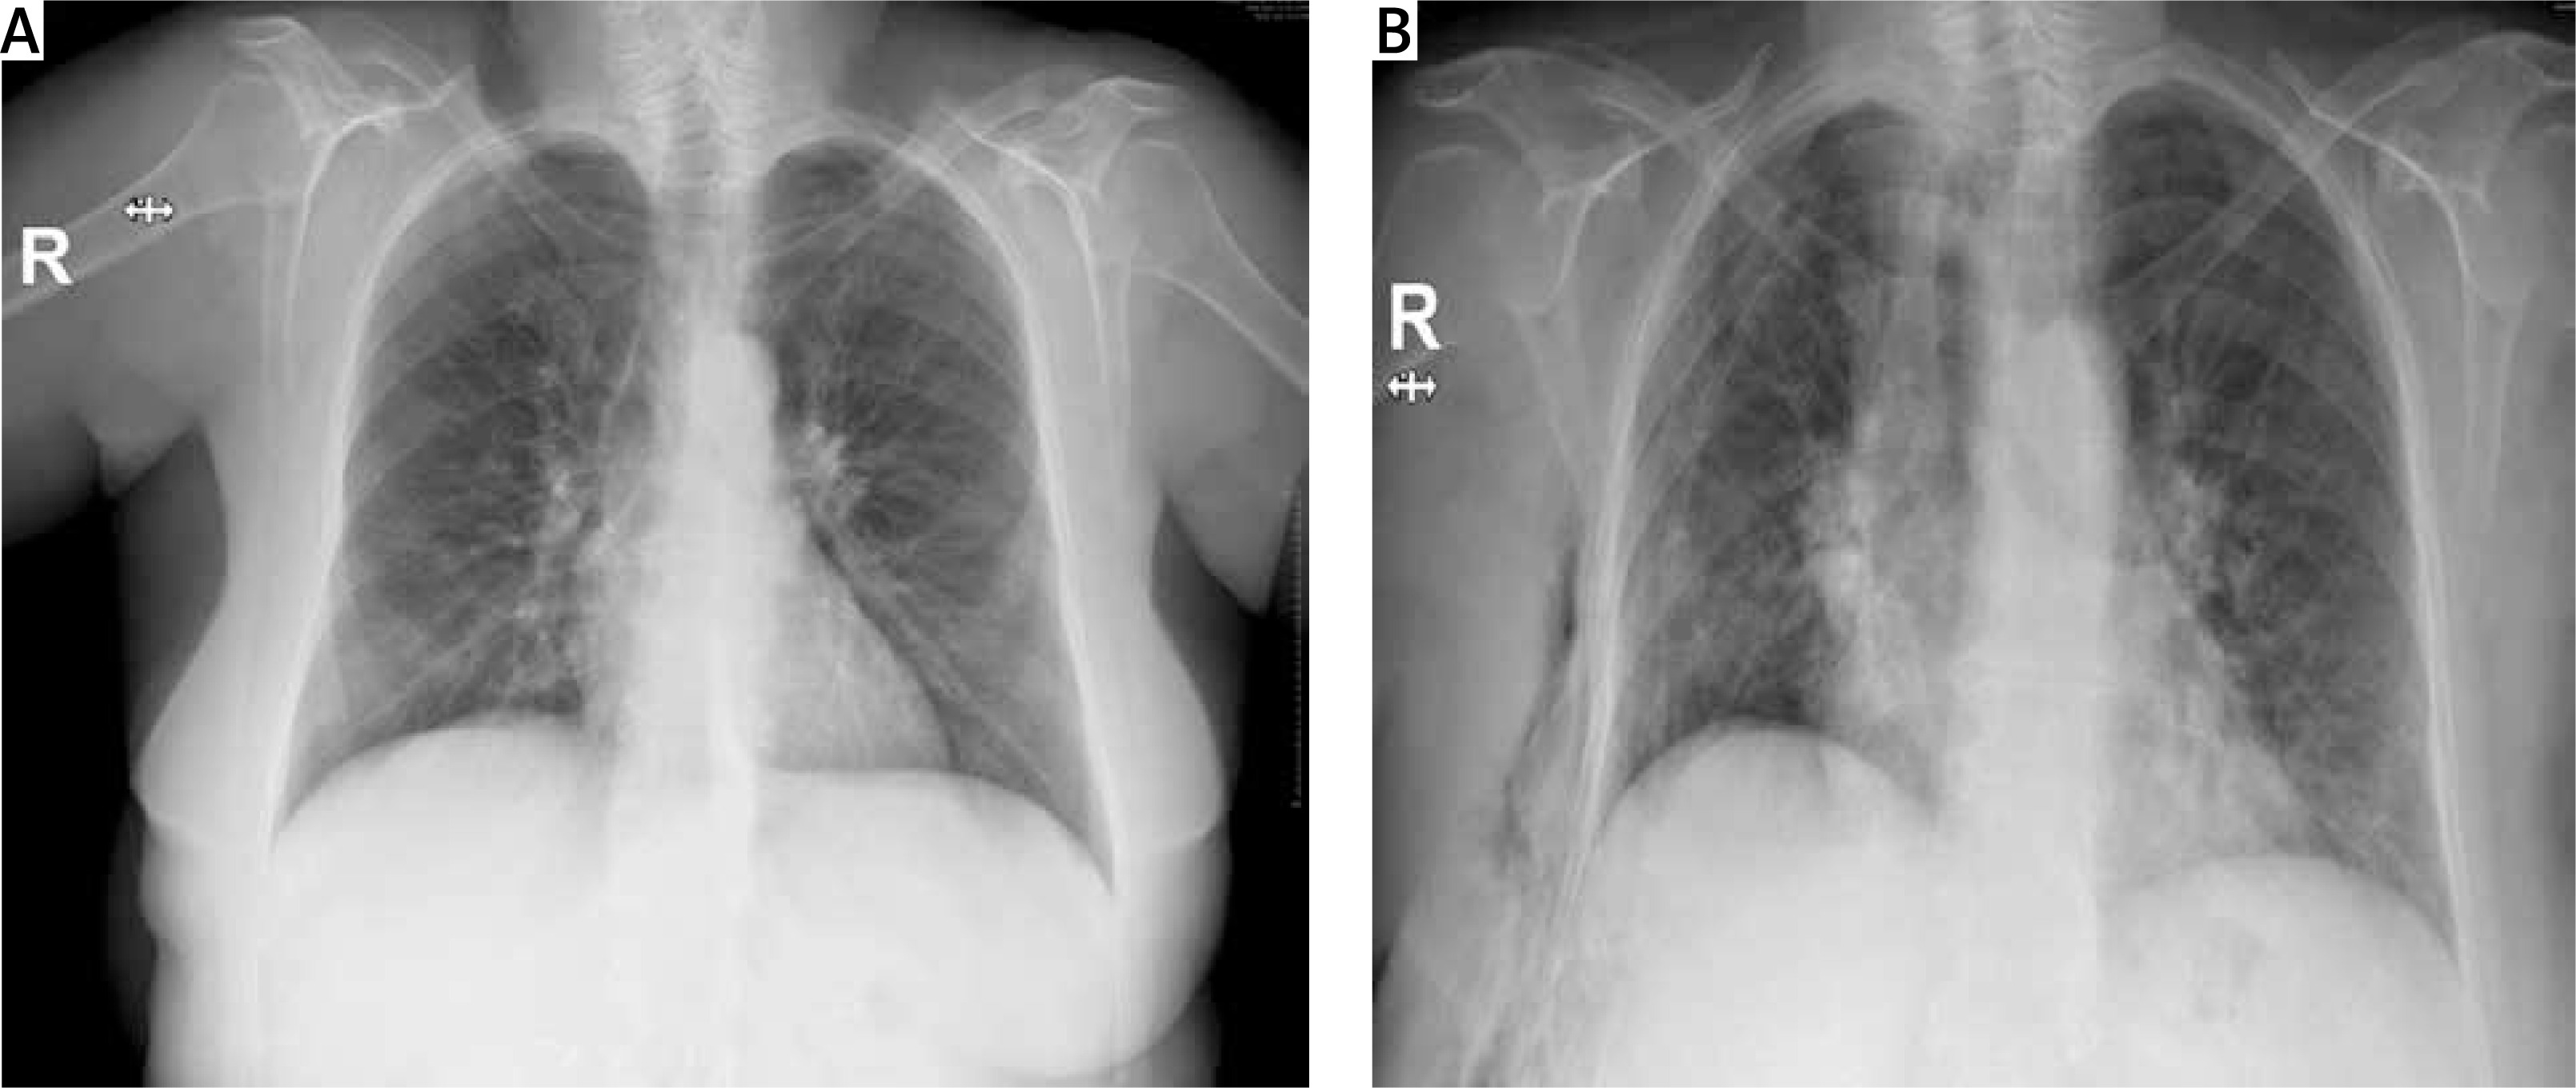

In the thoracic computed tomography of a 63-year-old female patient, a nodule with irregular margins was present in the inferior part of the upper lobe of the right lung. A transthoracic biopsy was taken from the nodule and the pathology result was reported as lung adenocarcinoma. The patient underwent right upper lobectomy and mediastinal lymph node dissection with uniportal VATS. Since the major and minor fissures were incomplete, they were intraoperatively separated with an endoscopic 60-4.8 parenchymal stapler. There was no decrease in hemoglobin value and no pathological finding on chest radiograph until postoperative day 4 (Figure 1). On postoperative day 4, the patient suddenly had hemorrhagic drainage. The patient had 500 ml of hemorrhagic drainage from the chest tube within 30 minutes. The patient was operated on in emergency conditions due to an appearance consistent with hematoma in the right hemithorax on chest radiograph (Figure 2) and decreased hemoglobin level. The uniportal VATS incision was extended posteriorly to provide access to the thorax. After the evacuation of approximately 1000 ml of hematoma, a bleeding focus was noted in the right internal mammary artery and was primarily sutured, and the bleeding was controlled. The bleeding originating from the internal mammary artery was thought to have occurred after the injury by the staple edge placed in the middle lobe to separate the minor fissure. The staple at the end was removed to prevent re-bleeding, and the area was sutured using 4-0 prolene suture. Intraoperatively, the patient received 4 units of erythrocyte suspension replacement. The hemoglobin value postoperatively reached a normal level. The patient’s postoperative chest radiographs showed expanded lungs with no pneumothorax or effusion. The patient with no pathological finding on the chest radiograph taken after the removal of the chest tube was discharged.

Figure 1

Preoperative posteroanterior chest radiograph and postoperative 4-day posteroanterior chest radiograph